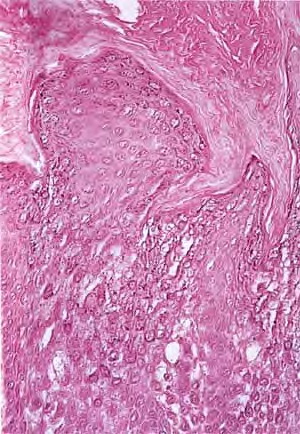

Histopathology. A characteristic histologic picture is seen in the epidermis and is referred to either as epidermolytic hyperkeratosis or as granular degeneration . It is present in bullous as well as in non bullous areas. There are variously sized clear spaces around the nuclei in the upper stratum spinosum and in the stratum granulosum. Peripheral to the clear spaces, the cells show indistinct boundaries formed by lightly staining material or by keratohyaline granules. A markedly thickened granular layer containing an increased number of irregularly shaped keratohyaline granules and compact hyperkeratosis is observed (14). When bullae form, they arise intraepidermally through separation of edematous cells from one another . The upper dermis shows a moderately severe, chronic inflammatory infiltrate. Mitotic figures are five times more numerous than in normal epidermis . Pathogenesis. Defects in keratin genes (KRT1 and KRT10) (16) are now known to be associated with this disorder. Mutations have been found in the carboxy terminal of the rod domain of keratin 1 and the aminoterminal of the rod domain of keratin 10 (17). The essential electron microscopic features are excessive production of tonofilaments and excessive and premature formation of keratohyaline granules; thus, at the periphery of the cells, numerous keratohyaline granules are embedded in thick shells of irregularly clumped tonofilaments (. The desmosomes appear normal, but the association of tonofilaments and desmosomes is disturbed, so many desmosomes are attached to only one keratinocyte instead of connecting two neighboring keratinocytes. Because of this disturbance in desmosomal attachment, blister formation takes place and real acantholysis occurs . Labeling with tritiated thymidine reveals greatly increased proliferative activity in the epidermis . It can be concluded that keratinization is both excessive and abnormal. Differential Diagnosis. Although the histologic picture of epidermolytic hyperkeratosis is diagnostic for the type of ichthyosis called epidermolytic hyperkeratosis, it is not specific for it. Hyperkeratosis is found also in several other seemingly unrelated conditions : epidermolytic keratosis palmaris et plantaris, solitary epidermolytic acanthoma, disseminated epidermolytic acanthoma, and linear epidermal nevus, usually of the systematized type. This latter entity was thought to be an entirely different condition than epidermolytic hyperkeratosis but with similar histologic findings. However, it is now known that epidermal nevi of the epidermolytic hyperkeratotic type are a mosaic genetic disorder of suprabasal keratin (l.e., point mutations of 10k alleles of epidermal cells in keratinocytes from lesional skin) that can be transmitted to offspring producing generalized epidermolytic hyperkeratosis . Epidermolytic hyperkeratosis can be an incidental finding in a variety of conditions